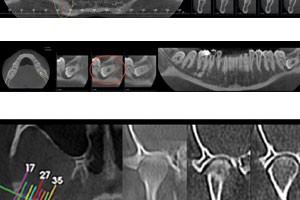

Quando è richiesto uno studio mirato delle Articolazioni Temporo Mandibolari (ATM), il semplice esame ortopanoramico non è più sufficiente e bisogna ricorrere a tecniche specifiche.

A questo scopo abbiamo dotato il nostro studio di un apparecchio radiografico digitale che ci permette di eseguire una serie di indagini volte a studiare le articolazioni nella loro completezza:

La stratigrafia dell’ATM è richiesta il più delle volte per la disfunzione temporo-mandibolare.

Tale patologia si riflette su un alterato meccanismo dell’articolazione nei movimenti di apertura o chiusura della bocca. Il sintomo tipico, “click articolare” è dovuto alla dislocazione anteriore o interna del disco articolare che perde il suo naturale rapporto anatomico con il condilo mandibolare. Al momento dell’apertura orale quando il condilo si muove in avanti e supera il disco anteriorizzato si avverte una vibrazione: click generalmente senza dolore poichè il disco articolare non possiede innervazione.

Il click, se trascurato, può progredire con usura del disco fino alla perforazione e all’insorgenza di artrosi mandibolare con degenerazione dei tessuti e importanti limitazioni nell’apertura orale. Il disco perforato genera un rumore ( di “sabbia” ) dato dallo sfregamento delle ossa in contatto e possono verificarsi episodi di dolore articolare per infiammazione traumatica.

Per una valutazione ancora più accurata della struttura condilo-mandibolare disponiamo della TC Cone Beam 3D per lo studio morfologico delle ATM che attraverso ricostruzioni tridimensionali permette di studiare le modifiche ossee del condilo (appiattimento, erosione, sclerosi, osteofitosi,riassorbimento), lo spazio interarticolare (normale, aumentato, ridotto, contatto osseo tra condilo e fossa mandibolare) e le modifiche ossee della fossa mandibolare.